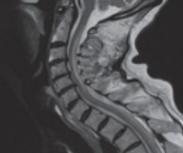

脊髓亞急性聯(lián)合變性